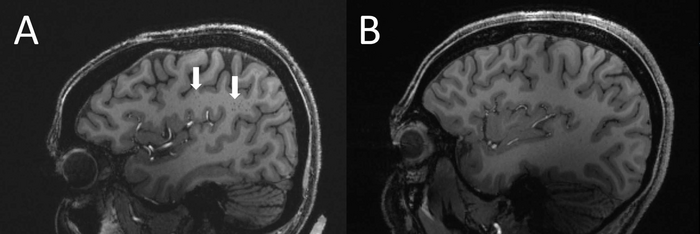

Увеличенные периваскулярные пространства у пациента с мигренью (слева) по сравнению с контрольной группой (справа). Изображение: RSNA, Wilson Xu

Статистический анализ показал, что количество расширенных периваскулярных пространств в полуовальном центре было значительно выше у пациентов с мигренью по сравнению с контрольной группой. Исследователи отмечают, что расширенные периваскулярные пространства могут быть признаком заболевания мелких сосудов.